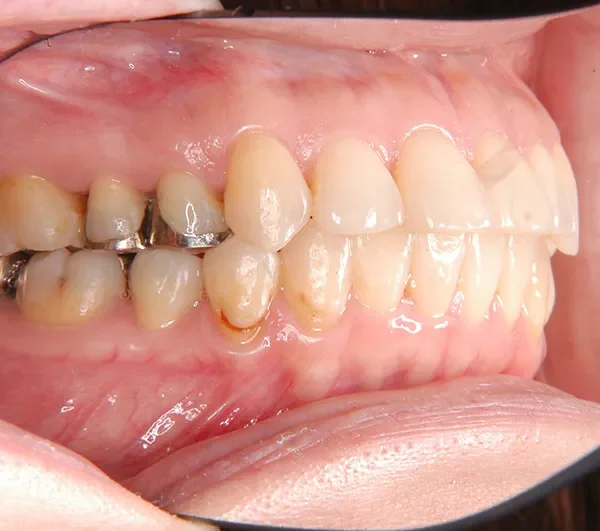

治療終了後

治療回数35回、2年8ヶ月の治療期間で矯正治療を終了しました。

噛み合わせが安定する事で、大きくなっていた咬筋が正常な大きさになり、顎のラインもシャープになり大変よろこばれていました。

また今回の症例は、歯科矯正用アンカースクリューを用いた治療の本に掲載されました。